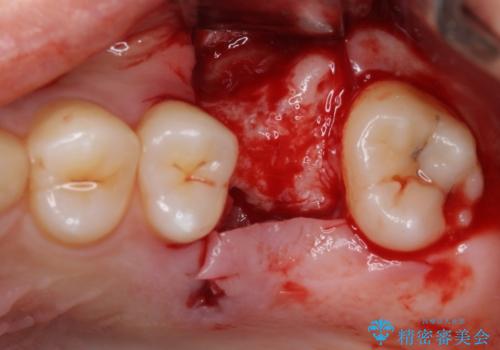

奥歯の虫歯は抜歯が必要であったので、矯正治療前に抜歯をし、矯正治療と並行してインプラントによる補綴治療を行うこととしました。